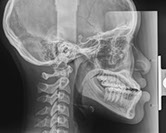

cephalometric

Cephalometric images (cephs) are used primarily in orthodontic diagnosis to measure the facial bones, including the jaws, to help determine treatment. Lateral cephs also show possible airway obstruction. PA cephs are used primarily to assess symmetry.